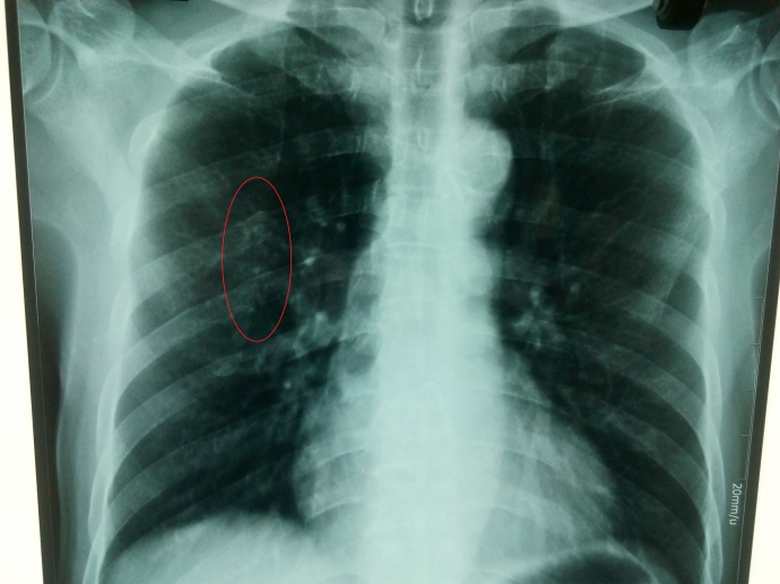

Phim X quang do BV quốc tế Vinh chụp ngày 24/3 và Bác sỹ Hường (BV quốc tế Vinh) chẩn đoán xương sườn bình thường (!?) |

Tuy nhiên, trong vai người nhà bệnh nhân, PV đưa phim X quang của ông Hoàng do Bệnh viện quốc tế Vinh chụp sang bệnh viện khác nhờ đọc thì kết quả lại bất ngờ. Một vị bác sỹ cho biết, “với phim X quang này nếu để xem tim phổi thì tạm được, nhưng để xem xương thì kém. Chụp xem tim phổi khác, chụp xem xương phải khác. Do đó, trên phim này cũng khó xem xương, nhưng có điểm lưu ý ví dụ như cung sau xương sườn số 5”.

Dư luận đang đặt câu hỏi, liệu bác sỹ Hường do trình độ kém nên không nhìn thấy dấu vết nghi vấn trên cung sau xương sườn số 5, hay là bác sỹ Hường biết nhưng đã làm ngơ, không thông báo cho ông Hoàng biết (!?).